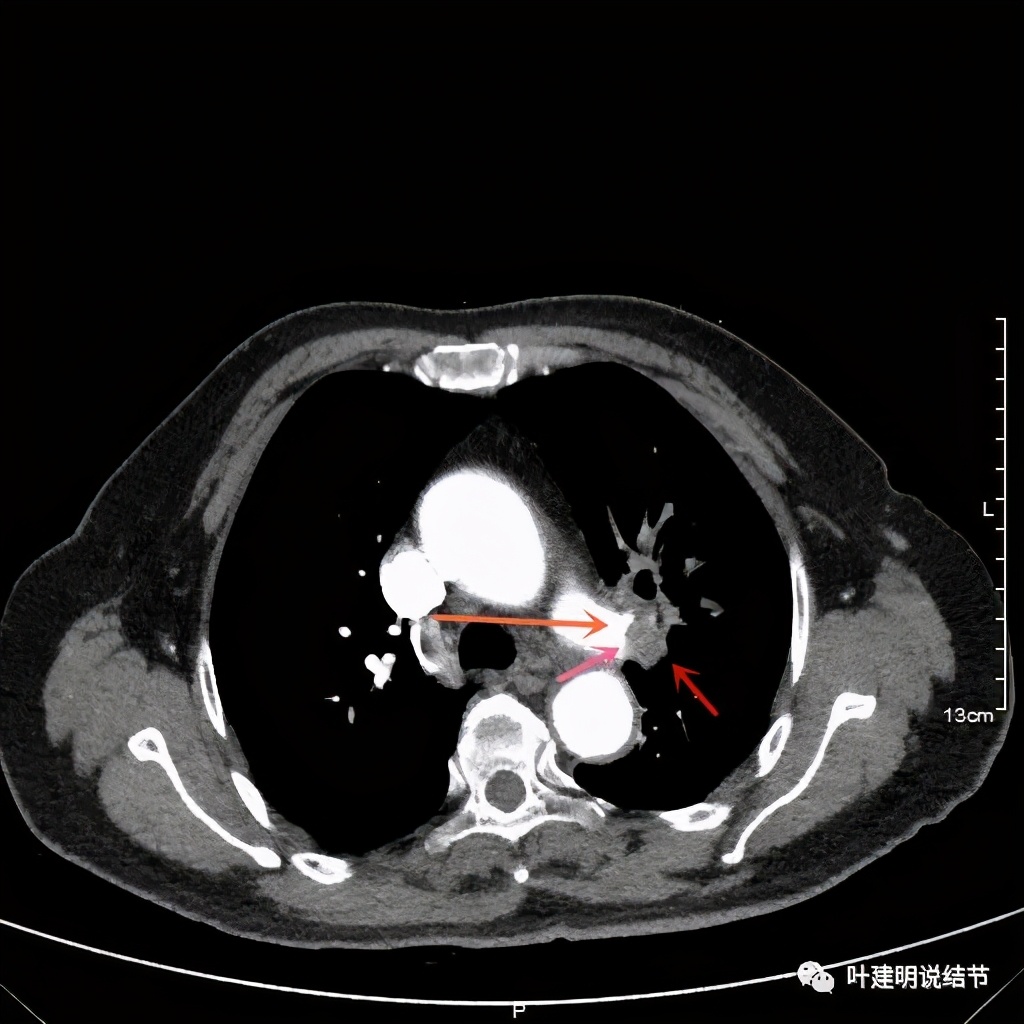

上图桔色箭头示左肺动脉分支处仍被软组织(原肿瘤所在)包绕,粉色箭头示肺动脉仍与肿瘤处关系密切

上图也示桔色箭头示左肺动脉分支处仍被软组织(原肿瘤所在)包绕,粉色箭头示肺动脉仍与肿瘤处关系密切

上图示肿瘤部位仍与肺动脉关系密切,似乎未能脱开,红色示肿瘤处